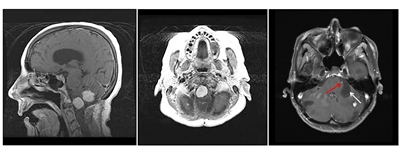

Hemangioblastomas are the most common disease manifestation in patients with VHL, affecting more than 70% of individuals. A prospective study assessed the natural history of hemangioblastomas.[16] The mean age at onset of central nervous system (CNS) hemangioblastomas is 29.1 years (range, 7–73 y).[17] CNS hemangioblastomas were most commonly seen in the cerebellum (45%), spinal cord (36%), cauda equina (11%), and brain stem (7%).[18] While sporadic hemangioblastomas are generally solitary in nature, the VHL-associated CNS lesions are often multifocal. After a mean follow-up of 7 years, 72% of the 225 patients studied developed new lesions.[18] Figures 2 and 3 depict cerebellar and spinal hemangioblastomas, respectively, in patients with VHL.

Figure 2. Hemangioblastomas are the most common disease manifestation in patients with von Hippel-Lindau disease. The left panel shows a sagittal view of brainstem and cerebellar lesions. The middle panel shows an axial view of a brainstem lesion. The right panel shows a cerebellar lesion (red arrow) with a dominant cystic component (white arrow).